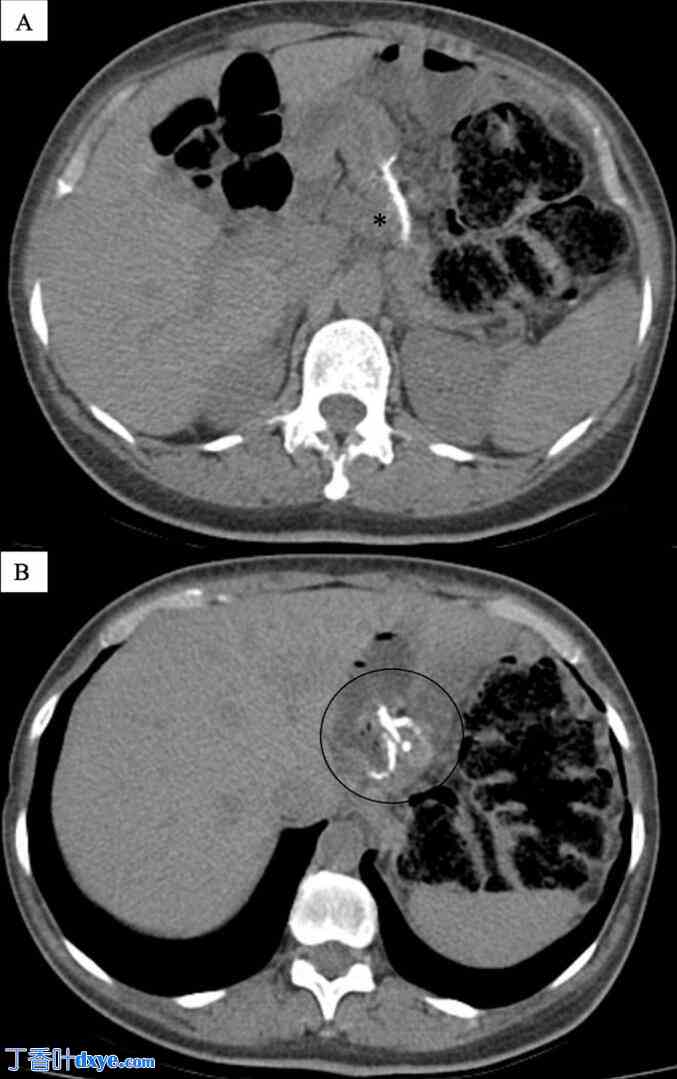

持续存在的症状促使医生进行进一步评估。采用双重对比技术的上消化道造影显示,胃囊较小,造影剂可畅通无阻地流入空肠袢(图1)。然而,观察到活动性胃食管反流,逆行造影剂到达食管中段。上消化道内镜检查显示符合食管炎的炎症改变以及复发性食管裂孔疝的证据。回顾腹部CT扫描报告,排除上消化道梗阻性病变或其他显著的解剖异常(图2)。

A-F. 上消化道造影(UGI)——双对比技术。

可见一个小的胃囊,造影剂顺利进入空肠袢。观察到逆行造影剂反流至食管中段,表明在肠-肠分流术前存在明显的胃食管反流。每幅图像均标注了造影剂摄入的时间。